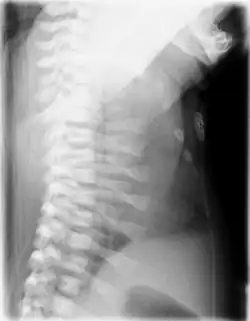

| CXR of a newborn with asphyxiating thoracic dysplasia. Note the short ribs. | |

Asphyxiating thoracic dysplasia (ATD), also known as Jeune syndrome, is a rare inherited bone growth disorder (autosomal recessive skeletal dysplasia) [1] that primarily affects the thoracic region. It was first described in 1955 by the French pediatrician Mathis Jeune.[2] Common signs and symptoms can include a narrow chest, short ribs, shortened bones in the arms and legs, short stature, and extra fingers and toes (polydactyly). The restricted growth and expansion of the lungs caused by this disorder results in life-threatening breathing difficulties; occurring in 1 in every 100,000-130,000 live births in the United States.[1][3]

Jeune syndrome is a rare genetic disorder that affects the way a child's cartilage and bones develop. It begins before the child is born and primarily affects the child's rib cage, pelvis, arms and legs.[5] Usually, problems with the rib cage cause the most serious health problems for children with Jeune syndrome. Their rib cages (thorax) are smaller and narrower than usual, which inhibits the child's lungs from developing fully or expanding when they inhale. The child may breathe rapidly and shallowly. They may have trouble breathing when they have an upper or lower respiratory infection, like pneumonia. Breathing trouble can range from mild to severe. In some children, it is not noticeable, aside from fast breathing; however, in others, breathing problems can be fatal. About 60% to 70% of children with this condition die from respiratory failure as babies or young children. Children with Jeune syndrome who survive often develop problems with their kidneys, and over time they may experience kidney failure.[2] As a result, few children with Jeune syndrome live into their teen years. Children with Jeune syndrome have a form of dwarfism. They are short in stature, and their arms and legs are shorter than most people's.[6]

Jeune syndrome is a rare autosomal recessive ciliopathy.[7] This diagnosis is grouped with other chest problems called thoracic insufficiency syndrome (TIS). Diagnosis of Jeune syndrome can be made as early as before birth if signs and symptoms are apparent on an ultrasound; however, diagnosis after birth usually occurs through X-rays and genetic testing, such as the tests found on the Genetic Testing Registry (GTR).[8]